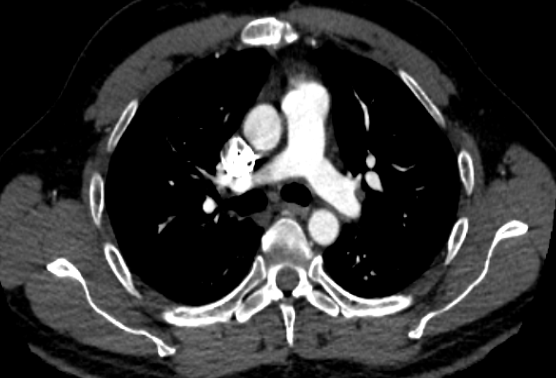

Bonjour, j'ai trouvé ce cliché d'angioscanner sur internet et je voudrais savoir si ce que je pense voir est bien juste !

Du coup là la flèche orange clair c'est la crosse de l'aorte et la flèche orange foncé c'est la veine jugulaire interne ??

Image

Oops trop débile, sur la dernière les deux plages rondes c'est l'aorte descendante et l'aorte ascendante, entre les deux c'est l'artère pulmonaire et à côté c'est la VCS :embarrassed:

Reste juste à m'aider pour la flèche orange foncé du deuxième scanner, merci !

La flèche orange foncée, c'est tout simplement la veine cave supérieure, non ? :)